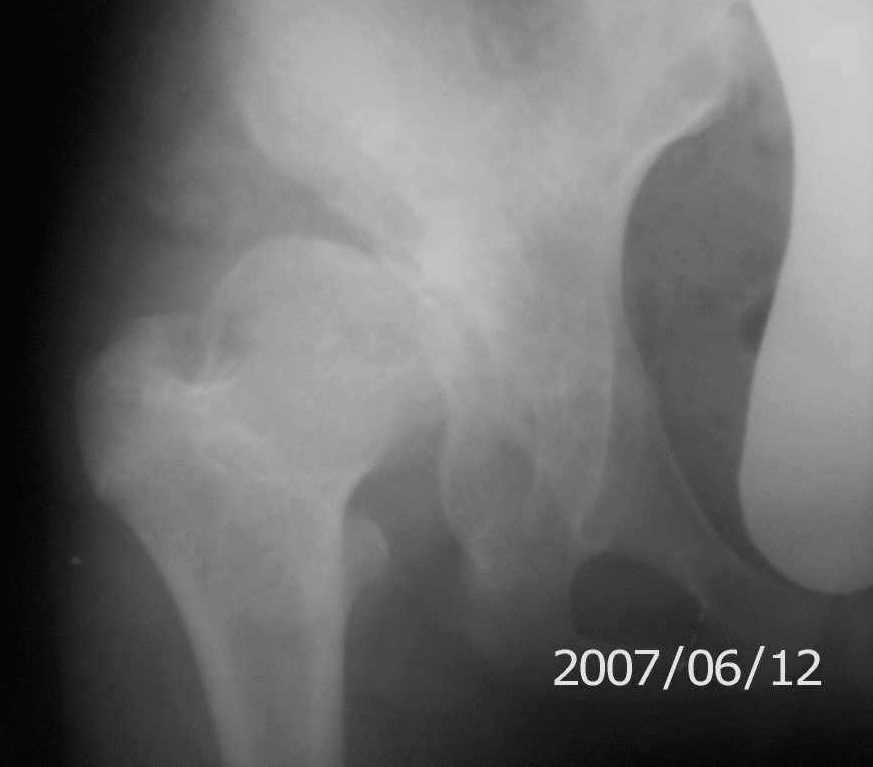

On x-rays coxa magna, shallow true + pseudoacetabulum.Options: salvage

Ацетабулюм крайне недоразвит. Есть высокий подвывих, можно даже сказать вывих с формированием ложного ацетабулюм. Для головки нет покрытия совсем и расположена она высоко.

На мой взгляд - SHORTENING OSTEOTOMY , VARUS если надо (на основании снимка во внутренней ротации), репозиция головки, CHIARI OSTEOTOMY или SHELF OPERATON Спасибо за интересный случай.